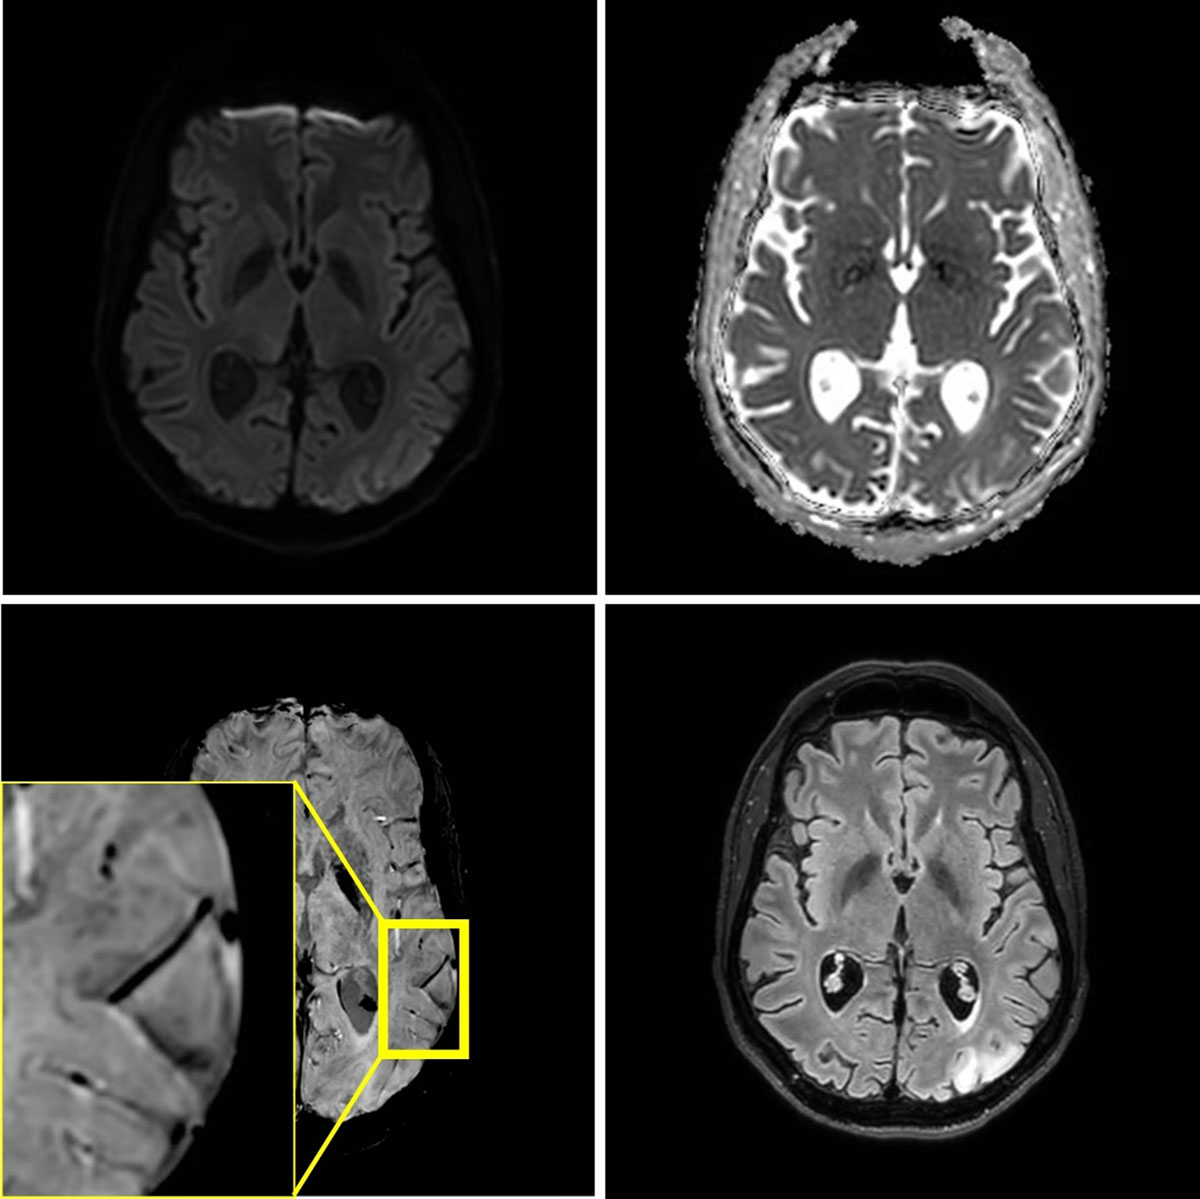

Figure 2

MRI at 3T performed three weeks later, because of a second stroke-like event. A similar lesion in the gyri of the left occipital lobe is present. Signal abnormalities in the previously affected area nearly normalized, but microhemorrhages persisted.